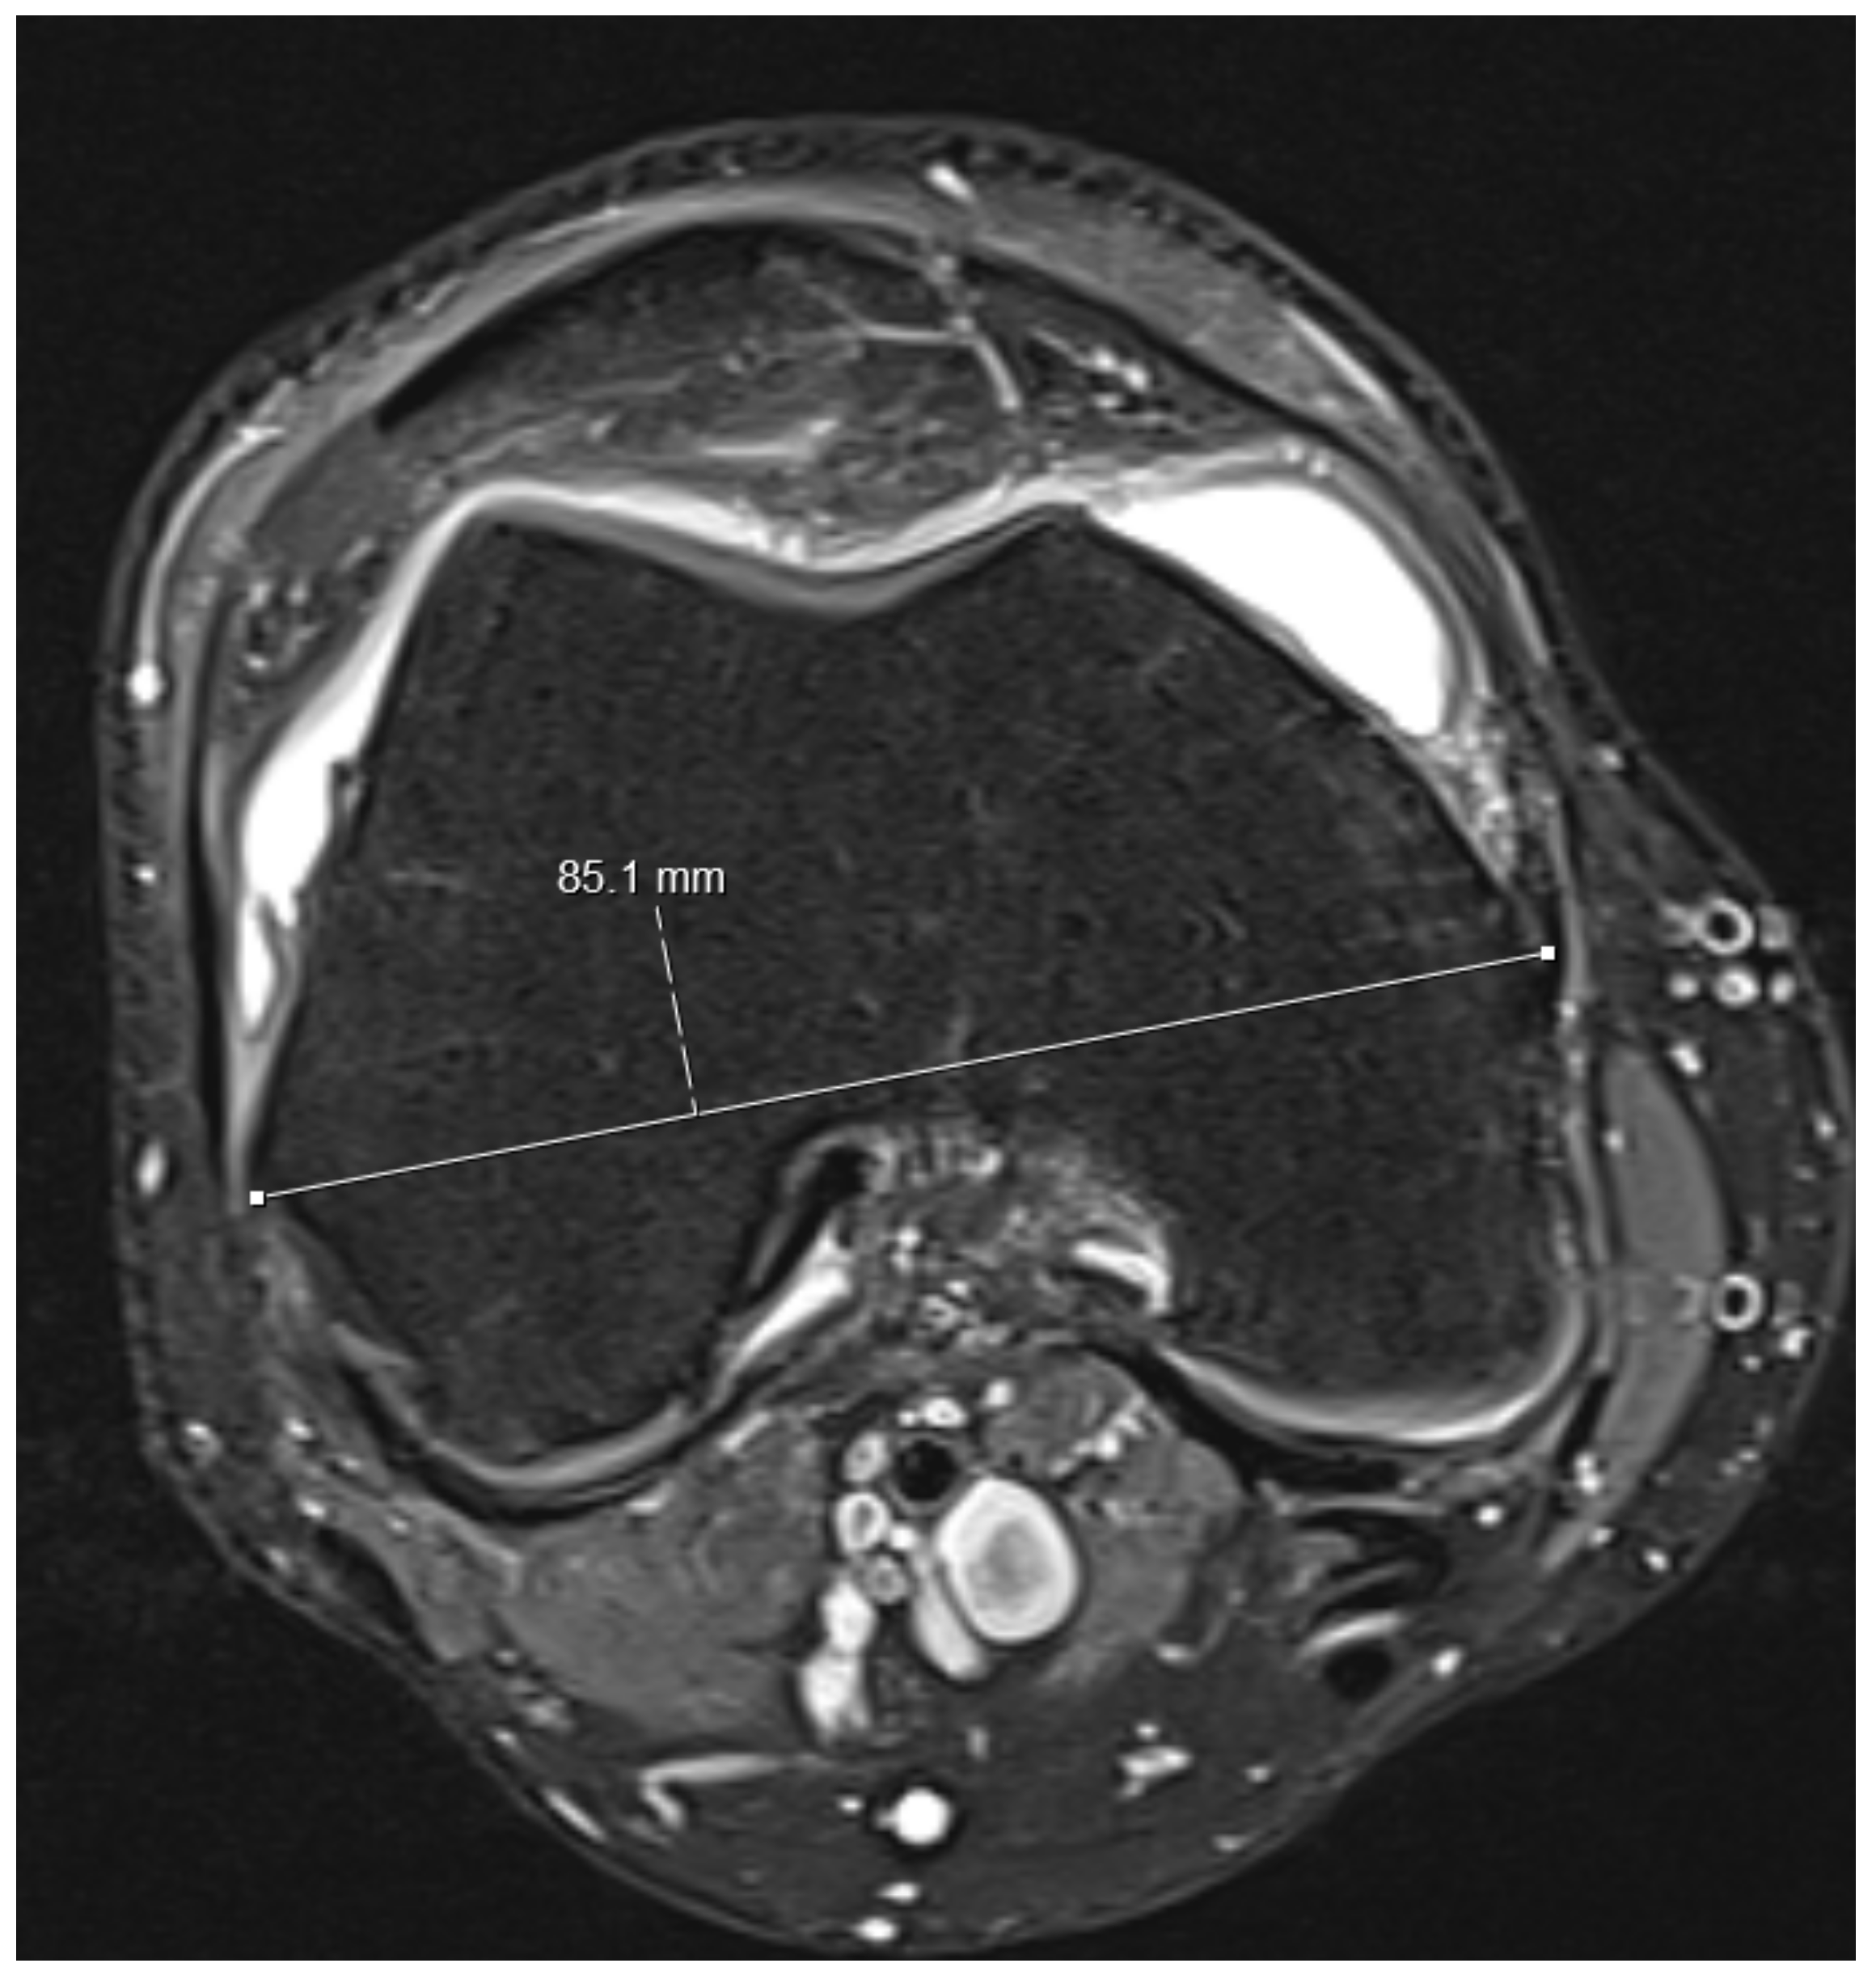

- The largest axial diameter of the distal femur at the level of maximal condyle diameter was measured and used for normalization (Figure 3).

Figure 3. The largest axial femur diameter was measured at the level of the condyles as indicated in the figure.